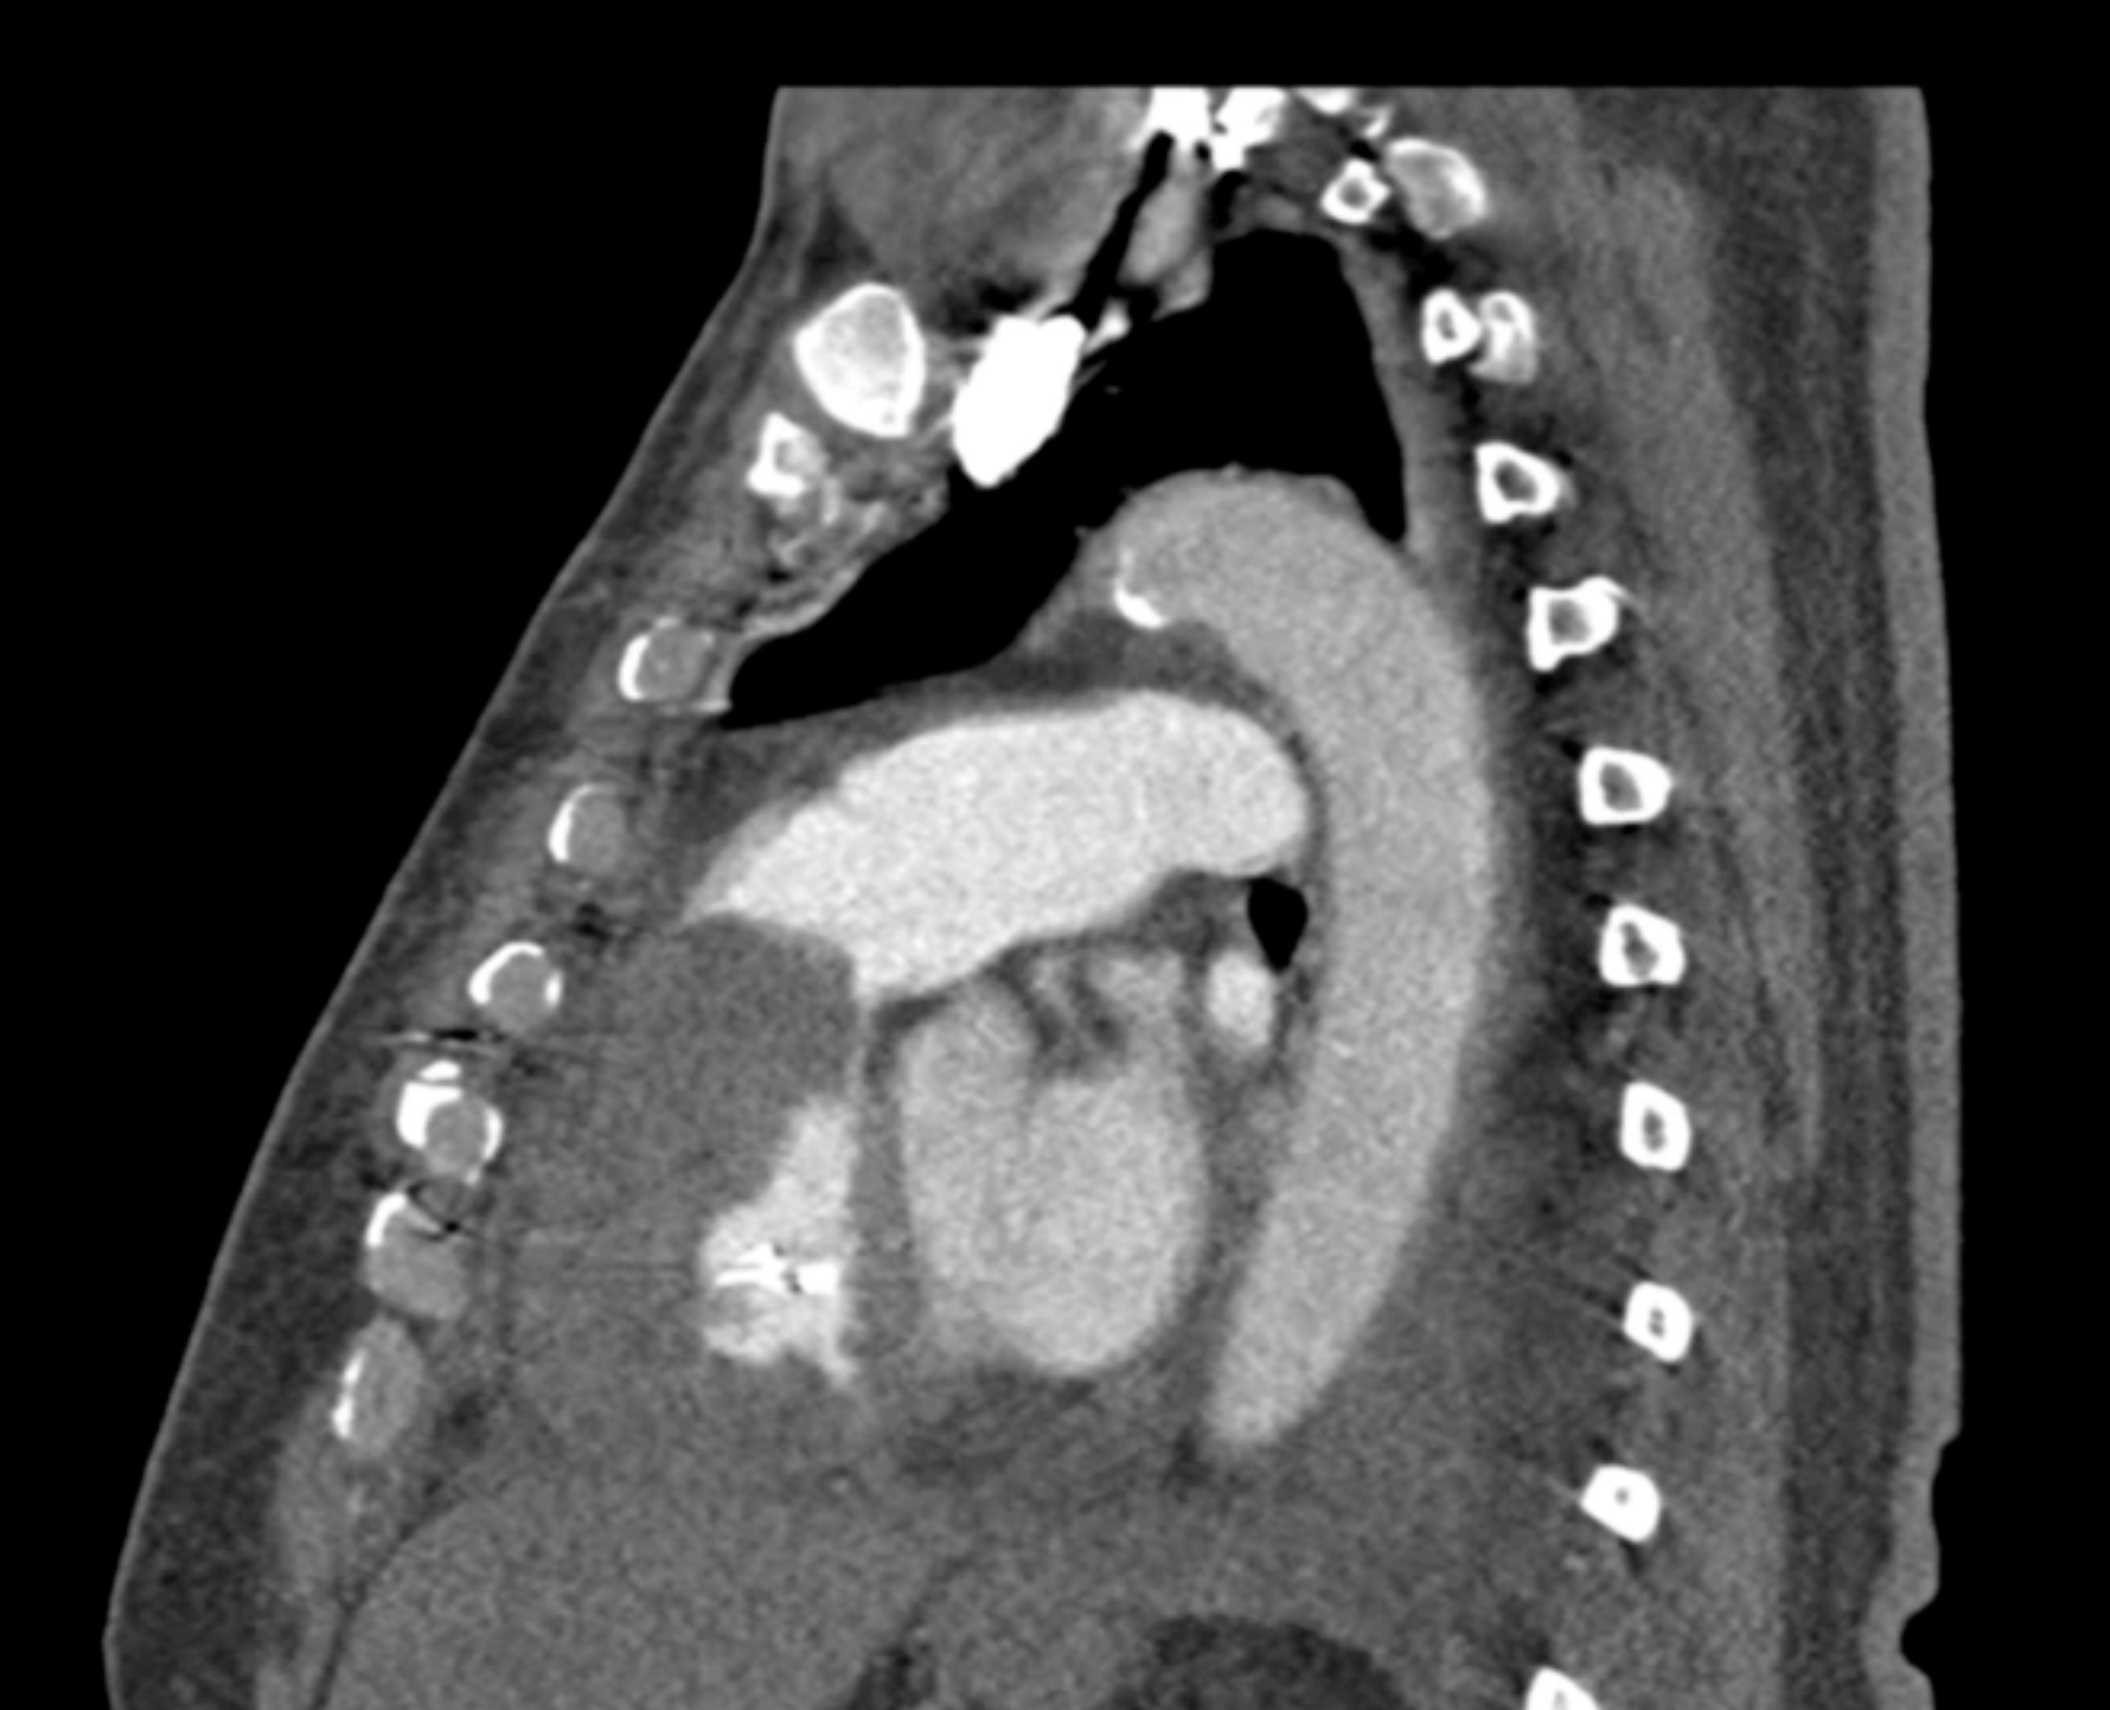

Primary Spindle Cell Carcinoma of the Right Ventricle